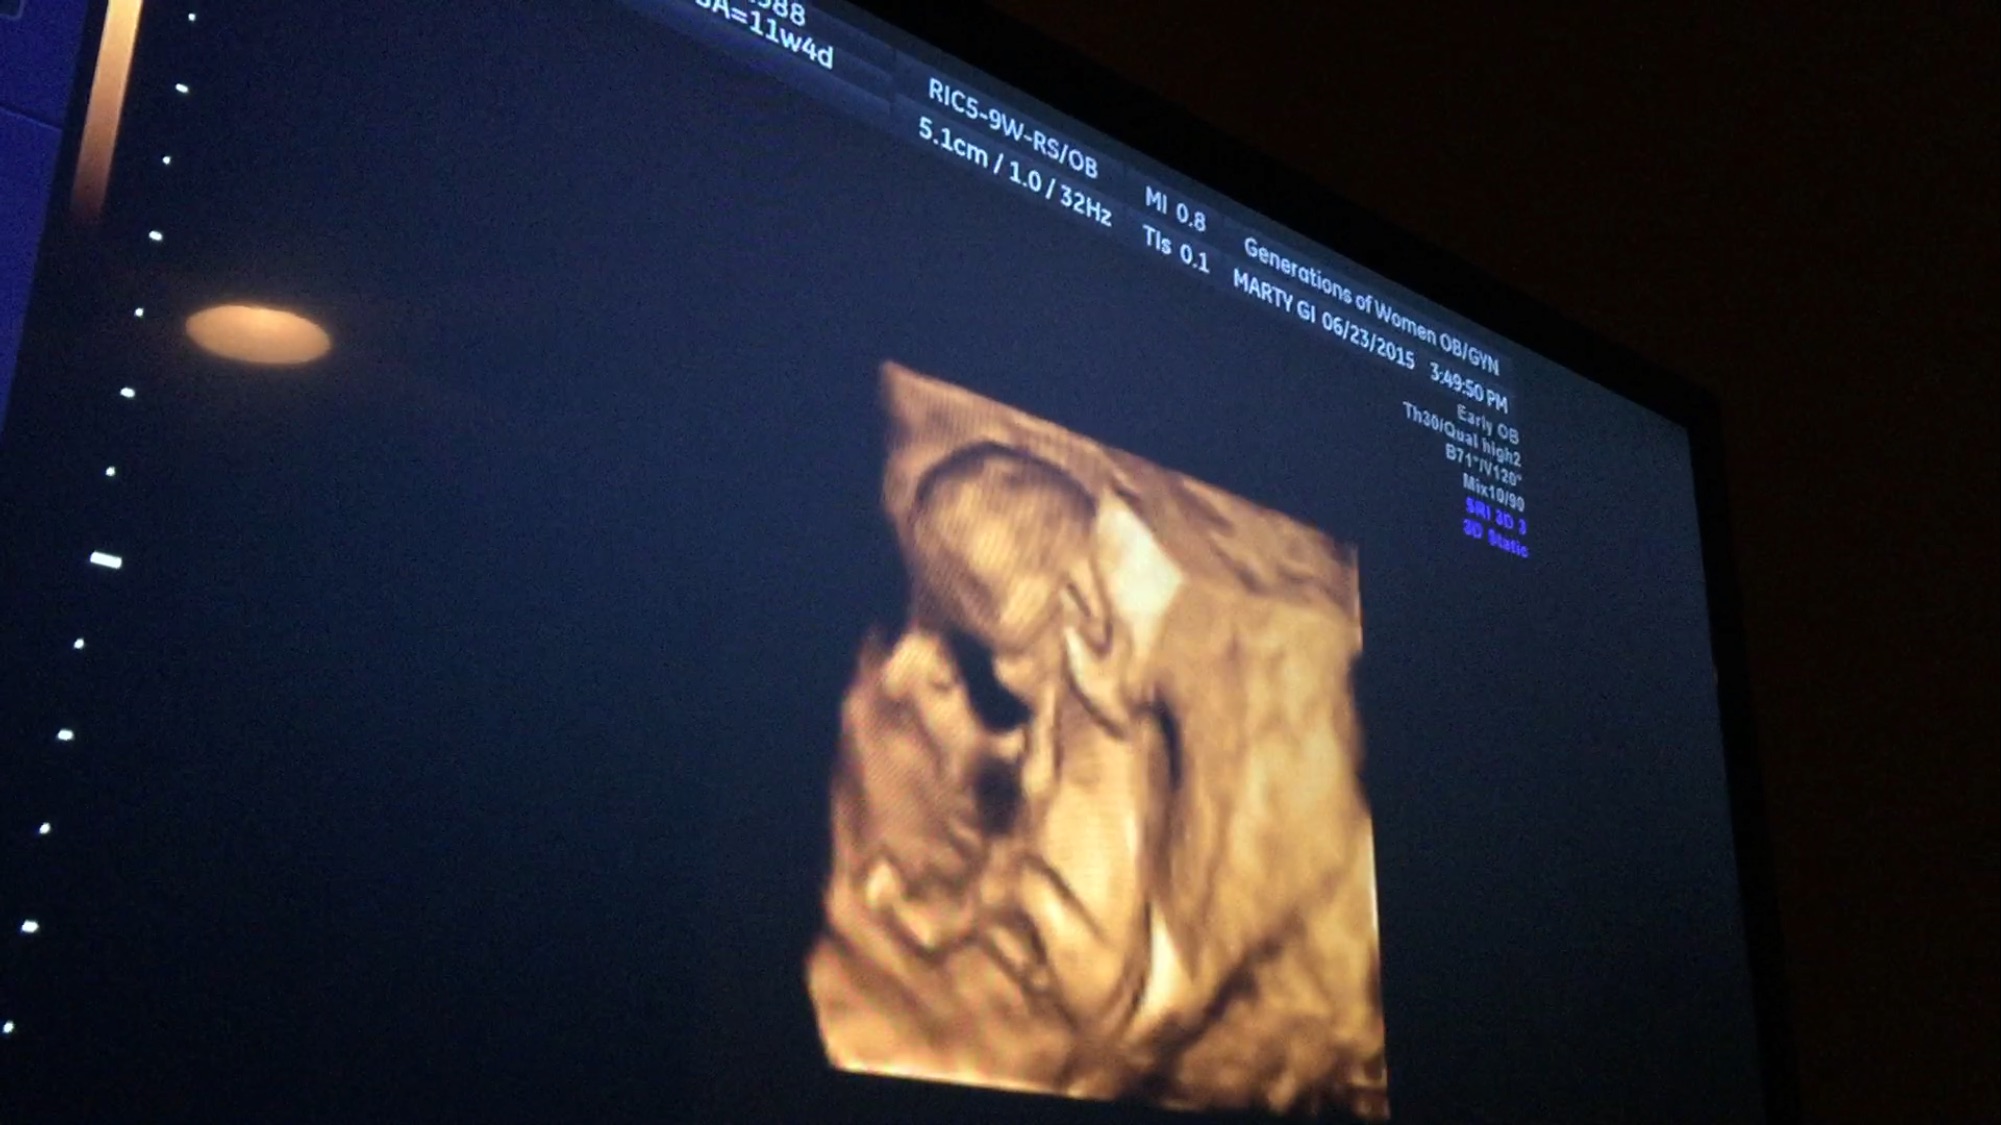

hubby is convinced it's a boy and so is most of his family. This is a screen shot from a video but there is an angle a split second before this one where it looks even bigger. What do you gals think???

https://www.baby2see.com/gender/external_genitals.html